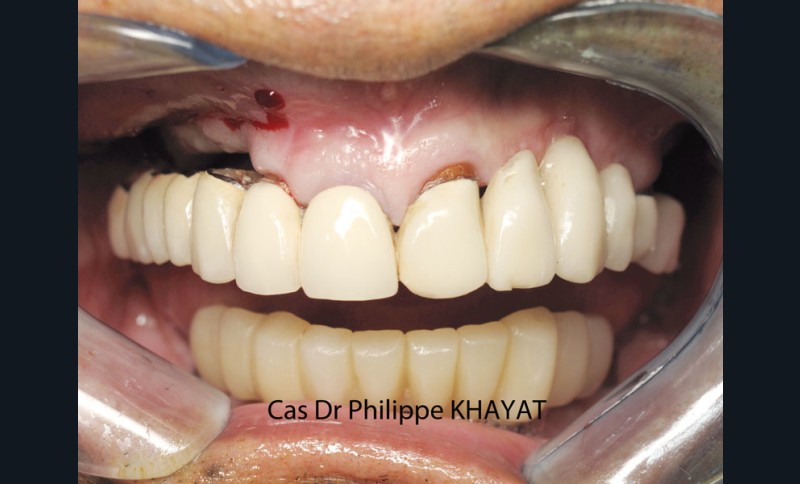

Philippe Khayat parlera de la « Mise en charge immédiate de l’arcade complète maxillaire » et il mettra l’accent sur les techniques qu’il a sélectionnées au terme de quatorze années d’expérience (fig. 1 à 4).